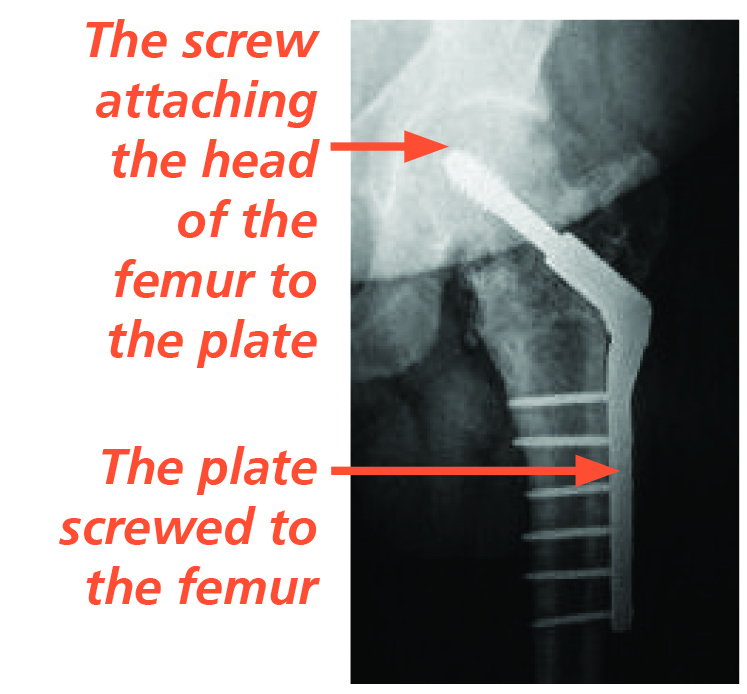

- A metal plate and screws (known as a Dynamic Hip Screw).

- An Intramedullary (IM) nail.